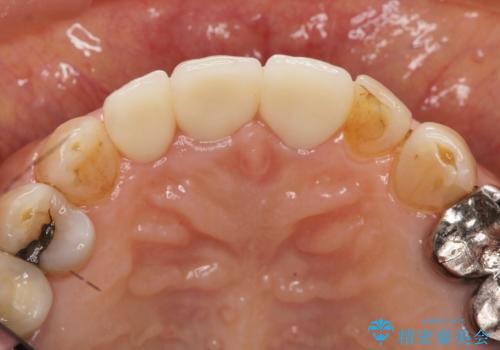

前歯の審美改善

- 40万円(仮歯・ファイバーコア・ジルコニアクラウン×3)費用は治療当時の料金となります

セラミック治療は外から見えるのはクラウンの色味・形態、歯肉の状態のみですが、X線撮影において現れるクラウンと歯牙の適合や、ファイバーコアの精度・根管充填の密度に、より長い予後を達成するための要素が含まれると考えます。